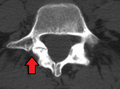

Spondylolisthesis L5/S1

Spondylolisthesis L5/S1 Spondylolisthesis L5/S1

Spondylolisthesis L5/S1 Spondylolisthesis L5/S1. Blue arrow normal pars interarticularis. Red arrow is a break in pars interarticularis

Spondylolisthesis L5/S1. Blue arrow normal pars interarticularis. Red arrow is a break in pars interarticularis Spondylolisthesis L5/S1

Spondylolisthesis L5/S1